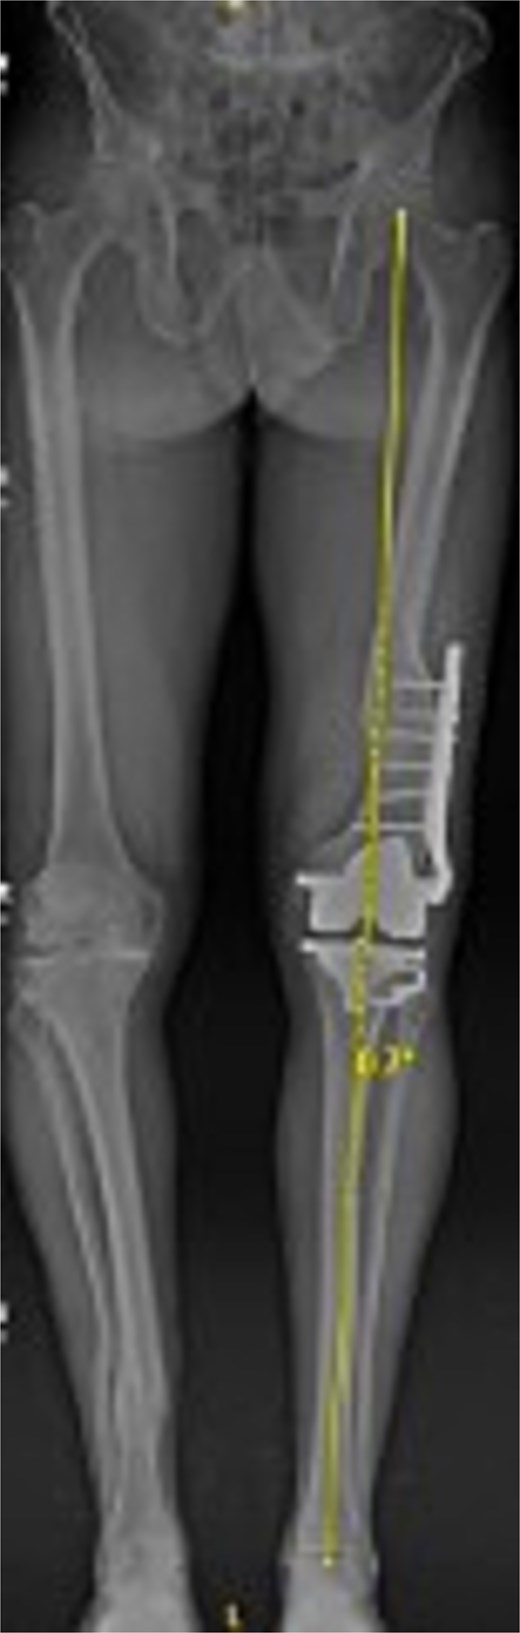

Preoperative radiographs revealed end-stage OA with osteophytes and subchondral sclerosis. Figure 1 shows the lateral view of the distal femur and knee. A healed malunion with significant recurvatum of 12° is evident, stabilized by a locking plate spanning the distal third of the femur. The plate and screws remained securely fixed, and the distal femur deformity altered the knee’s sagittal alignment with minimal impact on the coronal alignment. The AP standing long-leg radiograph (Fig. 2) demonstrated varus alignment of ~3°. The extra-articular deformity was located ~10 cm proximal to the knee joint line. No loosening of hardware or nonunion was noted. After discussing options, including staged deformity correction versus one-stage TKA, the decision was made to proceed with a single-stage TKA as the patient had a reasonable range of motion without hyperextension and a preference to avoid multiple surgeries.

Preoperative standing AP radiograph of the patient’s lower extremities. The left femur has a lateral plate from a prior fracture. There is 3° varus alignment of the arthritic left knee. The femoral deformity is primarily in the sagittal plane, and the retained hardware is visible.

Figures 3 and 4 show a postoperative lateral and AP radiograph of the left knee. The patient was able to fully extend his knee after surgery and instructed to weight bear as tolerated until his two-week follow-up. Patient-reported outcome measures were completed at 2 year follow up (Table 1) with no reported complaints or issues at that time.

Postoperative AP bone length films 1 year after robotic-assisted TKA with hardware retention. The new femoral and tibial components are in place. The retained femoral plate is visible along the lateral cortex of the femur. Postoperative mechanical alignment of the left leg is 0.7°.